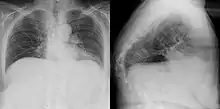

Gibbus deformity in a chest X-ray (frontal and lateral) of an old woman.

Gibbus deformity is a form of structural kyphosis typically found in the upper lumbar and lower thoracic vertebrae, where one or more adjacent vertebrae become wedged. Gibbus deformity most often develops in young children as a result of spinal tuberculosis and is the result of collapse of vertebral bodies.[1][2][3] This can in turn lead to spinal cord compression causing paraplegia.[4][5]

Gibbus deformity is included in a subset of structural kyphosis that is distinguished by a higher-degree angle in the spinal curve that is specific to these forms of kyphosis. Other conditions within this subset include Pott's disease and Scheuermann kyphosis, but gibbus deformity is marked by an especially sharp angle. Viewed from behind, the resulting hunchback is more easily seen when bending forward.[10] A kyphosis of >70° can be an indication of the need for surgery and these surgeries can be necessary for children as young as two years old, with a reported average of 8 years of age.[9]